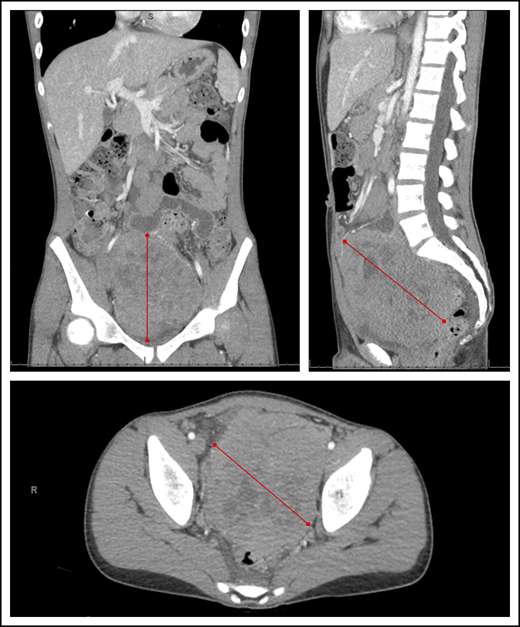

Abdominal computed tomography imaging demonstrating a large heterogeneous mass centered within the pelvis and lower abdomen in a child with BL. Red lines represent the extent of the lymphoma mass from its outer edges.

Current standards of BL treatment in SSA are still primarily based on the successes of pioneering trials from the 1970s with cyclophosphamide as the backbone agent, without differentiation of staging or risk group.25,27,36-41 Survival rates have plateaued over the past 40 years, and efforts to improve have stalled since then. Contemporary efforts to improve outcomes within the cyclophosphamide-based paradigm have included the addition of various low doses of MTX,42-44 vincristine,45 doxorubicin, and prednisone.17,20,46,47 The collective experience has demonstrated cohort survival rates ranging from 30% to 50%, with mortality primarily attributed to tumor progression or recurrence (Table 1). Patients with stage I/II BL have achieved survival of 40% to 60%, whereas survival for stage III/IV BL (typically involving the abdominal cavity, bone marrow, or CNS) has remained <30%.26,38,40,41,48-50 This is particularly relevant because numerous studies in SSA have demonstrated that abdominal mass has become at least as common as jaw mass as a presenting feature of endemic BL (Figure 1).17,20,51,52